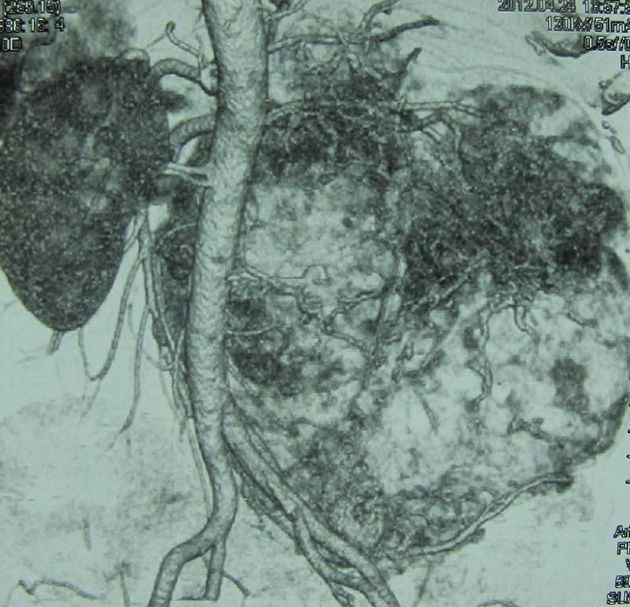

Опухоль правой почки (компьютерная томография с сосудистым контрастированием)